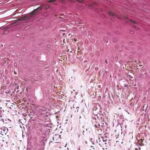

onset of a nodule, with development of ulceration . However, some acral melanomas may be deeply invasive while remaining quite flat because the thick stratum corneum seems to act as a barrier to exophytic growth. Histopathology. The lesions are termed lentiginous because the majority of the lesional cells are single and located near the dermal-epidermal junction, especially at the periphery of the lesion . However, usually some tumor cells can be found in the upper layers of the epidermis, especially near areas of invasion in the center of the lesions. The histologic picture differs from that of lentigo maligna because of irregular acanthosis, the lack of elastosis in the dermis, and the frequently dendritic character of the lesional cells . Early in situ or microinvasive lesions may show, especially at the periphery, a deceptively subtle histologic picture consisting of an increase in basal melanocytes and hyperpigmentation with only focal atypia of the melanocytes. However, in the center of the lesions, there is usually readily evident uniform, severe cytologic atypia. There may be a lichenoid lymphocytic infiltrate that may largely obscure the dermal-epidermal junction, and in some cases this may be so dense as to simulate an inflammatory process. In most of the lesions, both spindle shaped and rounded, pagetoid tumor cells are seen, and, in many cases, pigmented dendritic cells are prominent. Pigmentation is often pronounced, resulting in the presence of melanophages in the upper dermis and of large aggregates of melanin in the broad stratum comeum. As in lentigo maligna, when tumorigenic vertical growth phase is present, it is often of the spindle cell type and not uncommonly desmoplastic and/or neurotropic. In |